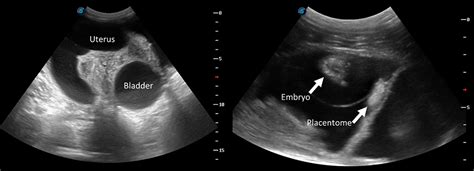

- Ultrasound: An ultrasound can confirm or rule out pregnancy by visualizing the uterus and ovaries. This is a very helpful tool in providing a clear answer to confirm. It can also help identify any underlying medical conditions, such as ovarian cysts or uterine fibroids.